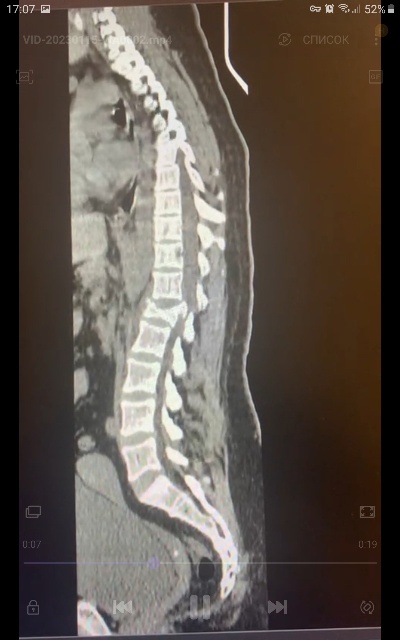

Новый клинический случай у травматологов КМКБСМП. Молодая женщина была доставлена в больницу с травмой позвоночника, которую получила во время спуска с горы на тюбинге.

Из практики врачей-травматологов травмы на тюбинге случаются, как правило, по одному сценарию. Для популярного зимнего развлечения пострадавшие выезжают за город и выбирают необорудованные для спуска склоны, где в результате столкновения получают серьезные травмы. В подобных обстоятельствах одна из пациенток БСМП на скорости выпала из «плюшки», в результате был серьезно травмирован позвоночник.

Оперативное лечение для пострадавшей проходило в несколько этапов. На каждом этапе травматологами была проведена транспедикулярная фиксация позвоночника системой позвоночных винтов, то есть в месте травмы позвонки были зафиксированы при помощи специальных имплантов.